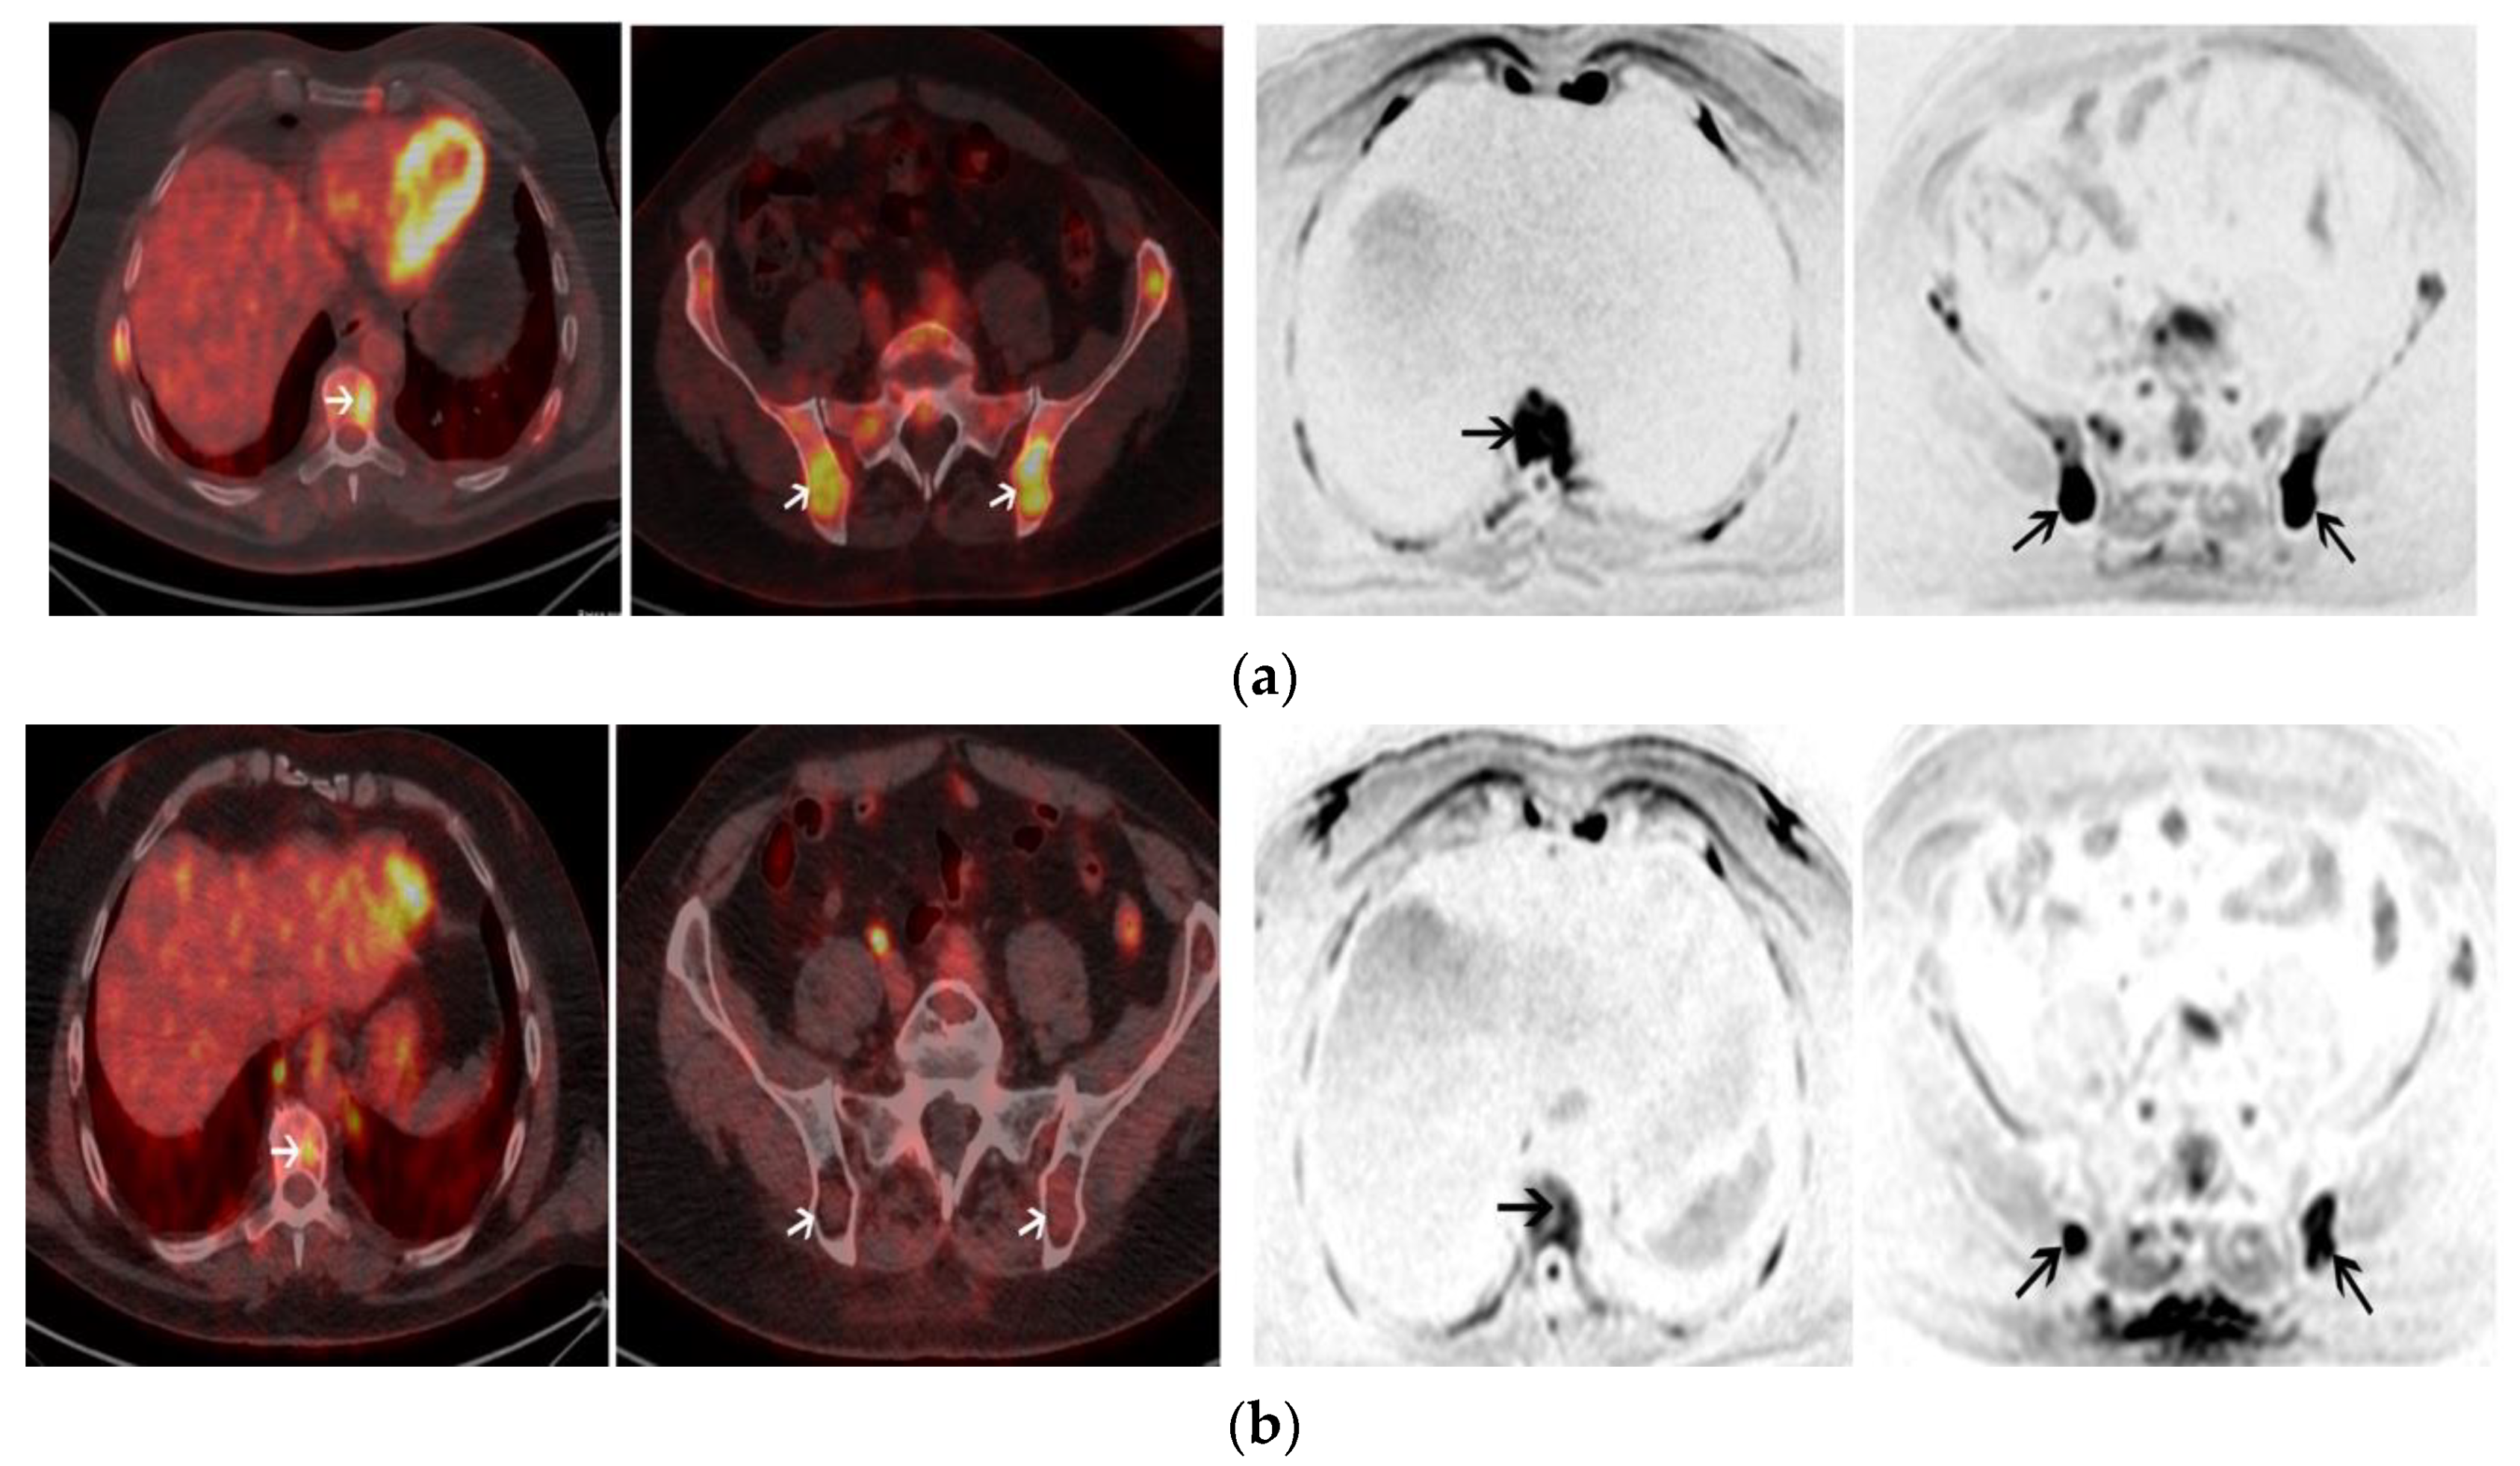

2.2. Post-Induction Chemotherapy Imaging

2.3. Post-ASCT Imaging